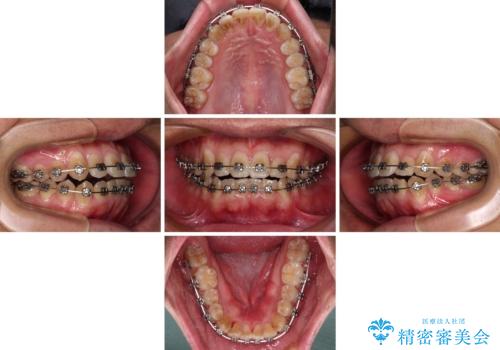

- メタルブラケット

- 1年3ヶ月

- 10-30回

治療終了直後は上下前歯が接触していましたが、舌の突出癖がなかなか改善されず、終了時の口腔内写真撮影時には、既に上下前歯に隙間ができてしまいました。